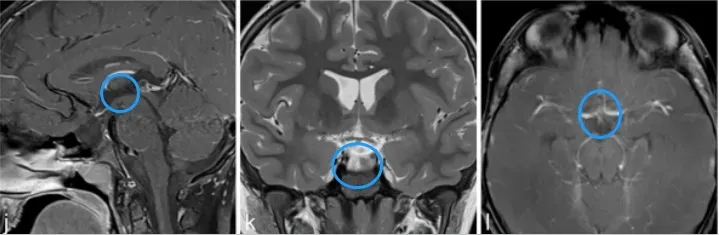

j、k、l图显示,肿瘤得到全切,术后2年无复发,目前孩子在接受激素替代疗法